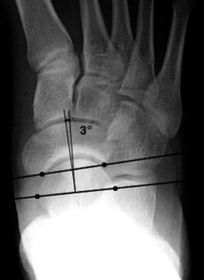

What is this angle called? Is this normal or abnormal? | AP - Talo-calcaneal angle This is normal |

What is this angle called? Is this normal or abnormal? | AP-Talo-calcaneal angle This is abnormal. The angle is reduced indicating pes cavo-varus |